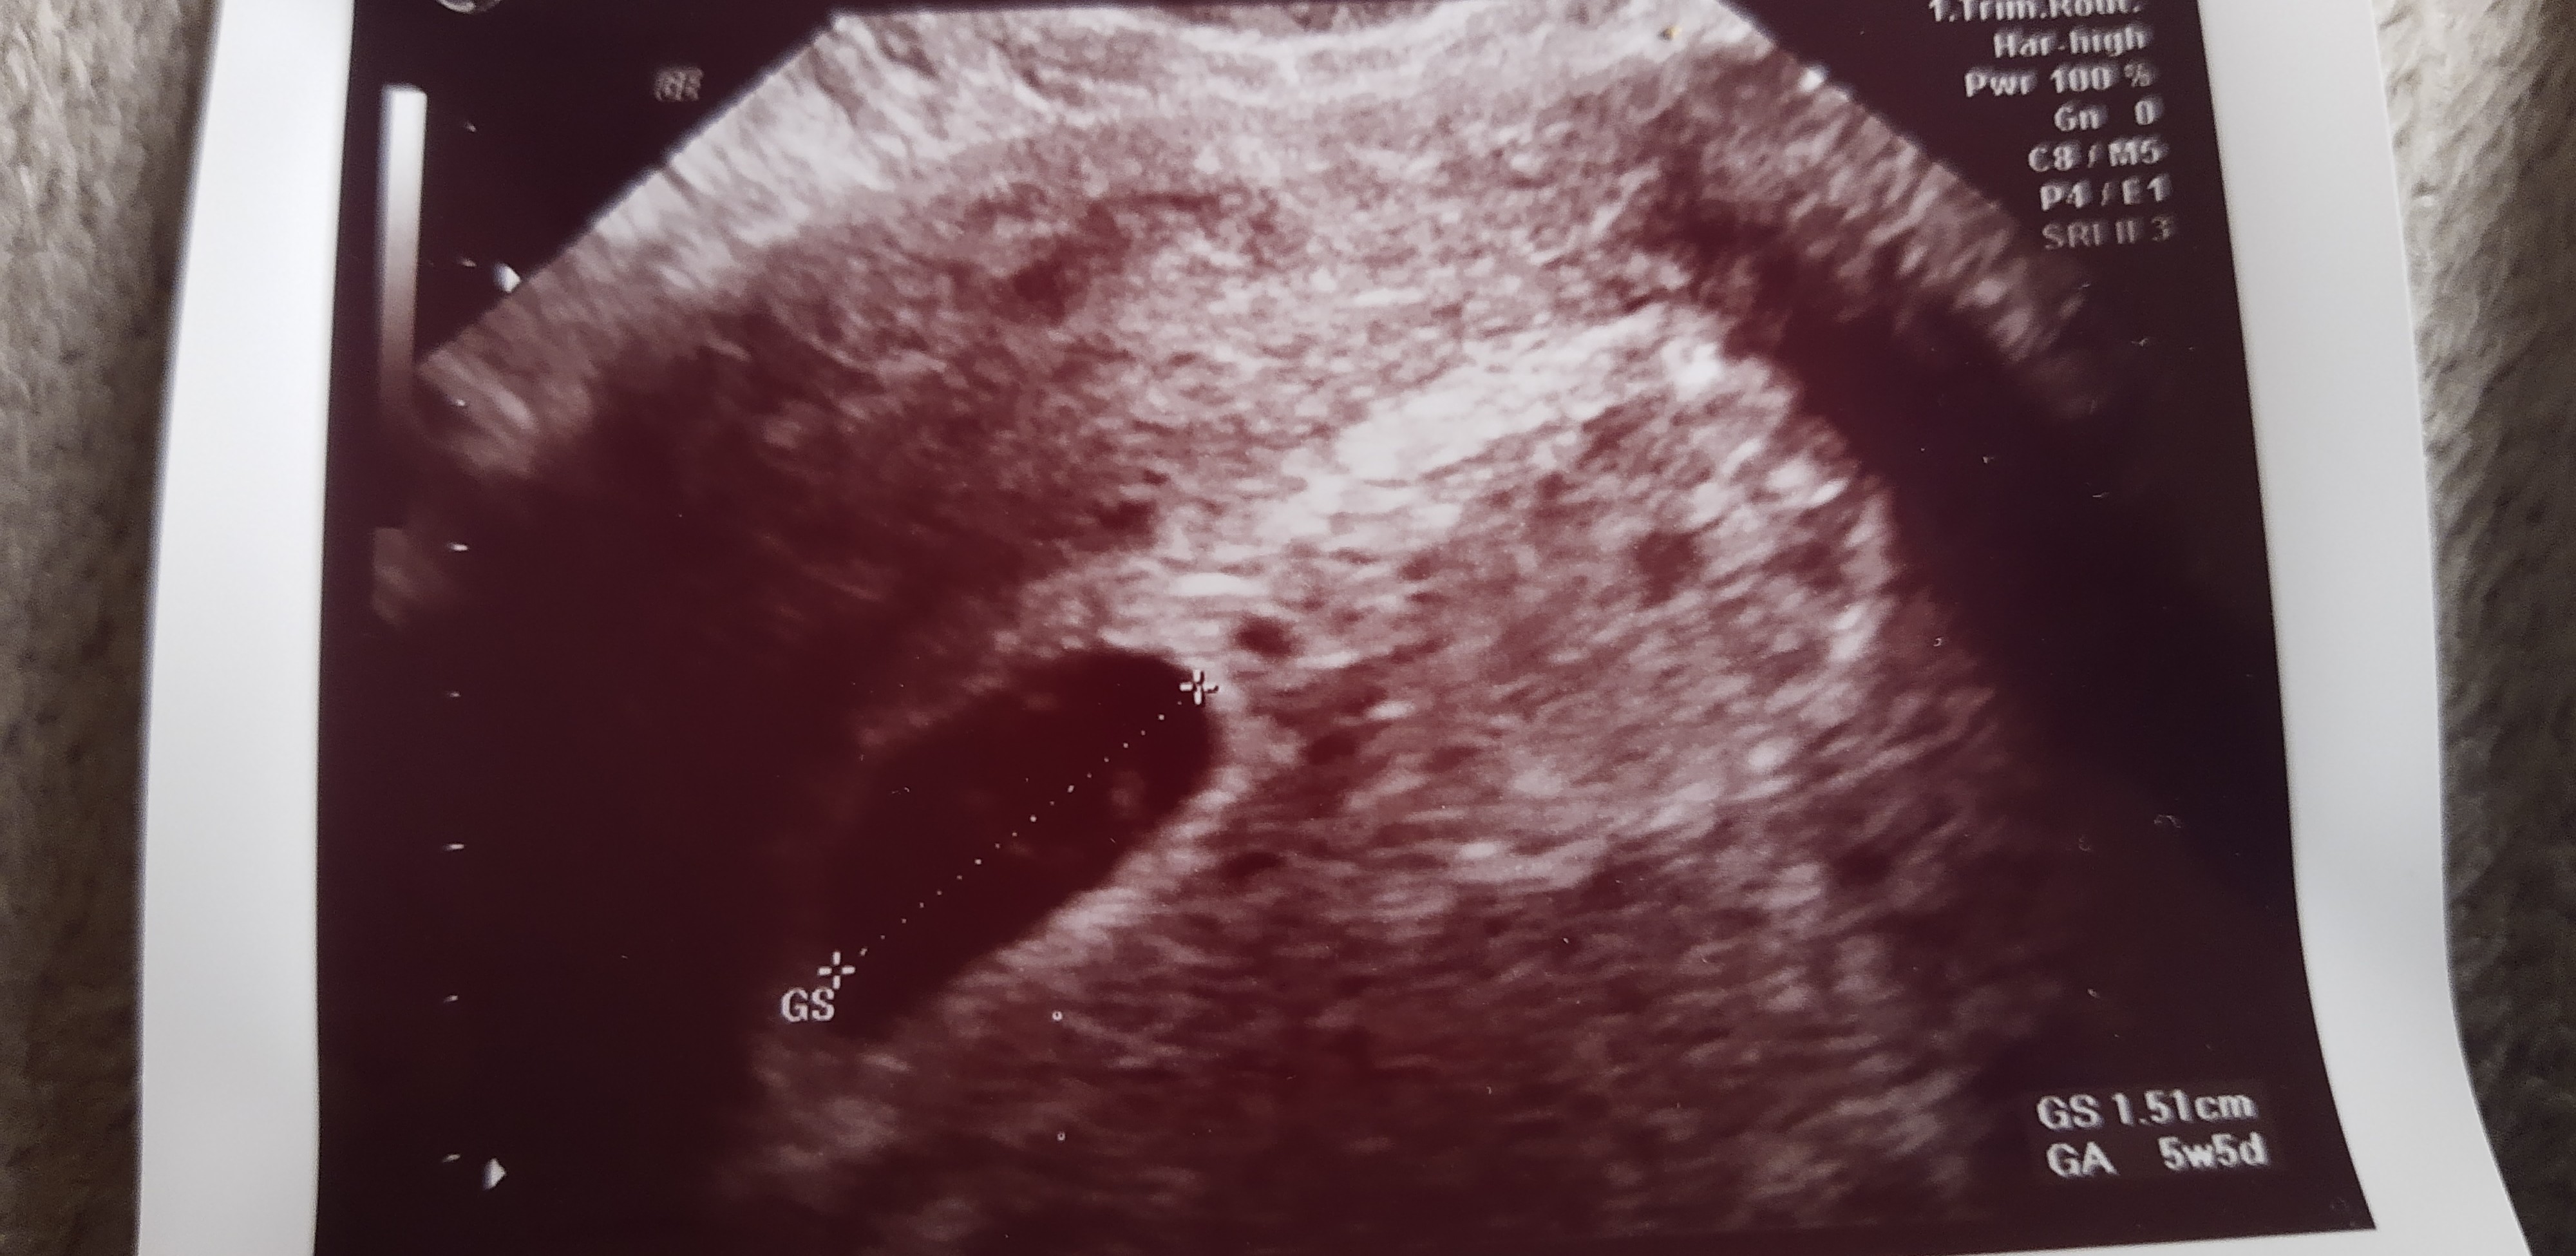

tutaj jest USG z zeszłej środy